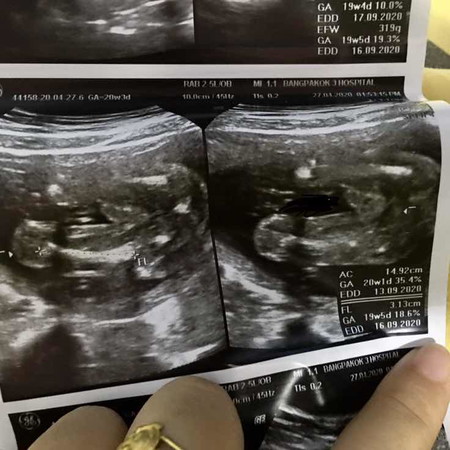

อันตร้าซาวด์เพศลูกแม่ๆช่วยดูหน่อยค่ะ

แม่บ้านนี้อยากรู้ว่าผู้หญิงรึชาย ใช่ชาย100%ไมค่ะ